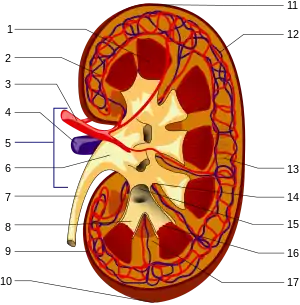

1. Renal pyramid • 2. Interlobular artery • 3. Renal artery • 4. Renal vein 5. Renal hilum • 6. Renal pelvis • 7. Ureter • 8. Minor calyx • 9. Renal capsule • 10. Inferior renal capsule • 11. Superior renal capsule • 12. Interlobular vein • 13. Nephron • 14. Renal sinus • 15. Major calyx • 16. Renal papilla • 17. Renal column

The functional substance, or parenchyma, of the human kidney is divided into two major structures: the outer renal cortex and the inner renal medulla. Grossly, these structures take the shape of eight to 18 cone-shaped renal lobes, each containing renal cortex surrounding a portion of medulla called a renal pyramid.[18] Between the renal pyramids are projections of cortex called renal columns.

The tip, or papilla, of each pyramid empties urine into a minor calyx; minor calyces empty into major calyces, and major calyces empty into the renal pelvis. This becomes the ureter. At the hilum, the ureter and renal vein exit the kidney and the renal artery enters. Hilar fat and lymphatic tissue with lymph nodes surround these structures. The hilar fat is contiguous with a fat-filled cavity called the renal sinus. The renal sinus collectively contains the renal pelvis and calyces and separates these structures from the renal medullary tissue.[19]